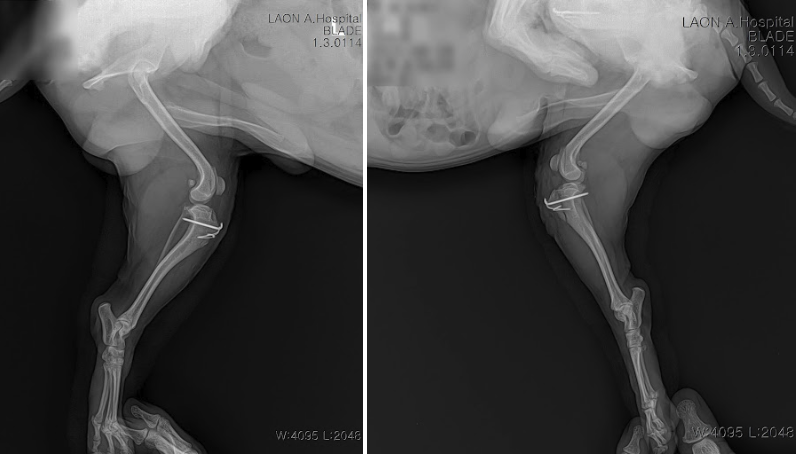

수술 후 방사선 사진 / 출처; 라온동물메디컬센터

수술 직후부터 입원 관리를 시작했고, 약 1주일간의 재활 치료를 병행하며 보행 회복을 도왔습니다. 퇴원할 즈음에 정상 보행이 가능한 상태까지 회복되었으며 보호자님께는 1개월간 운동 및 산책 제한 지침을 안내드렸습니다. 특히 집안에서 뛰거나 격하게 노는 행동은 삼가야 하며, 무리한 산책 역시 회복에 방해가 될 수 있음을 강조했습니다.